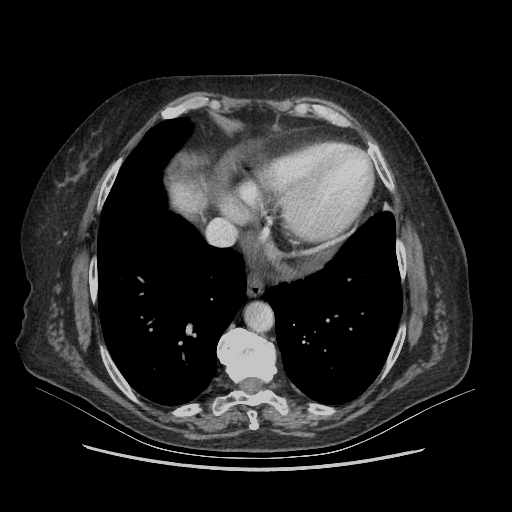

Original NATIVE CT scan (input)

No window - Raw intensity values

Reconstructed NATIVE CT scan (cycle consistency)

Original VENOUS CT scan

Generated VENOUS CT scan (A→B translation)